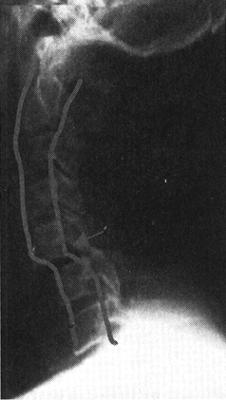

(一)X线平片和X线体层摄影

X线平片是脊柱损伤后的最基本和最重要的影像学检查方法,主要观察脊柱骨折和脱位情况。X线平片具有简单、易行和快速等优点,且可在不搬动疑似急性脊髓损伤患者的情况下在床边拍摄。X线平片空间分辨率高,骨骼结构成像清晰,目前仍是脊柱脊髓损伤检查的首选的影像学检查方法(图7-1)。临床上绝大多数的脊柱创伤骨折、关节脱位和半脱位都可通过普通X线的适当体位的投照而发现(图7-2)。脊柱常规投照位置有前后位、侧位和左、右斜位等。高质量的照片是诊断的最基本条件,如果一次照片不能满足诊断的需要,应调整相应的投照条件、胶片位置、球管中心以及投照角度重复拍摄,直至满意为止。对于怀疑有脊柱脊髓损伤患者应该在尽可能少搬动患者的情况下进行X线照片,尽量避免由于搬动病人而造成脊髓损伤加重。由于X线平片是投照部位解剖结构的重叠图像,限制了对复杂骨结构,特别是中轴骨骼解剖细节的显示,易漏诊细微而重要的骨折和错位。

图7-1 正常颈椎X线侧位片:正常颈椎前、中、后三柱连线光滑连续,中、后柱连线之间为脊髓所在

图7-2 C5以上前脱位,中、后柱连线显示在C5水平处明显狭窄,表明颈髓在此处受压